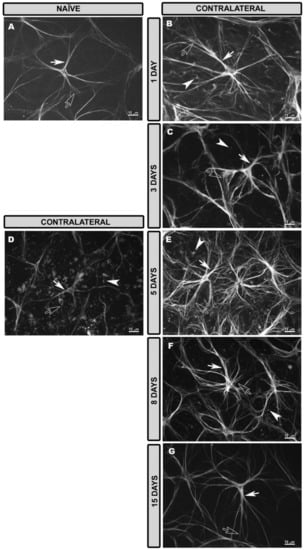

3.3. Morphological Changes in Retinal Macroglia of Contralateral Eyes at Different Time Points after OHT Induction

3.4. Morphological Changes in Retinal Macroglia of OHT Eyes at Different Time Points after OHT Induction